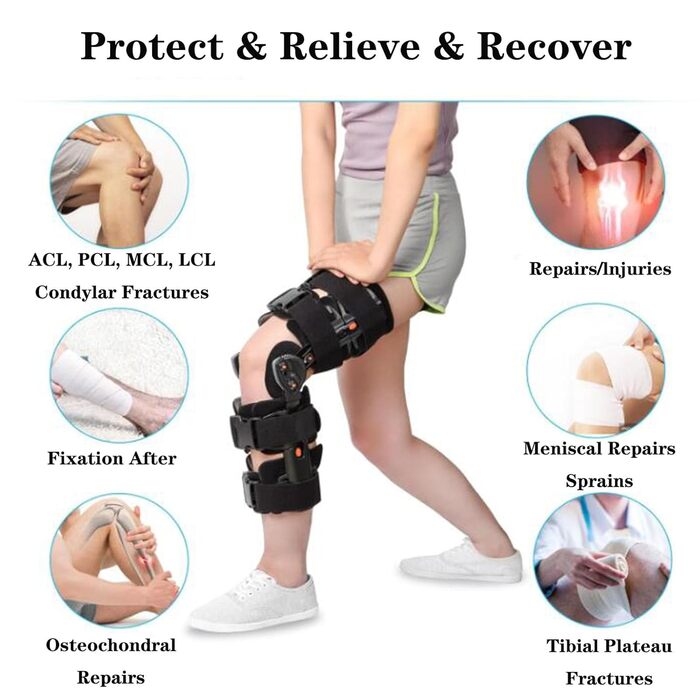

Опис Колінний ортез SFKLYU з шарніром регульований післяопераційний колінний ортез стабілізатор ноги для чоловіків і жінок, ортопедичний захисний ортез, стабілізатор, один розмір, B

- Напіввідкрита конструкція: шарнірний колінний бандаж легкий, але міцний і забезпечує виняткову підтримку. Відкрита конструкція шарнірного наколінника для післяопераційного коліна підходить для правої або лівої ноги, а регульований клейкий ремінь забезпечує комфортну посадку для чоловіків і жінок.

- Легкі та дихаючі: Нековзна підкладка та регульований ремінець з дихаючої тканини гарантують, що вам не буде душно та слизько протягом усього дня. Він не тільки легкий, але й забезпечує сильну, спеціалізовану підтримку. Він забезпечує стійкий ефект відновлення, але не заважає вашій повсякденній діяльності.

- -10-90 регульована фіксуюча ручка: Шарнірний колінний бандаж з регульованою фіксуючою ручкою може контролювати або обмежувати діапазон рухів під час відновлення та реабілітації після операції, щоб запобігти повторному травмуванню. Двосторонні налаштування діапазону рухів можна регулювати в межах -10-110 згинання та -10-90 розгинання, щоб задовольнити конкретні потреби пацієнтів.

- Легко носити: Вам потрібно лише закрити/відкрити пряжку, щоб закінчити надягання та зняття. Після початкового налаштування він дуже простий у використанні. Цей розвантажувальний колінний бандаж універсальний і легко підходить для широкого кола пацієнтів. Його можна використовувати для лівої та правої ноги, а довжина регулюється, тому ви можете змінювати розмір відповідно до свого зросту.

- Застосування: Підходить для відновлення після операції на коліні, травм внутрішніх і зовнішніх зв'язок та задньої хрестоподібної зв'язки або післяопераційного відновлення. Також підходить для розпушування коліна та післяопераційної реабілітації при артриті, переломах тощо.